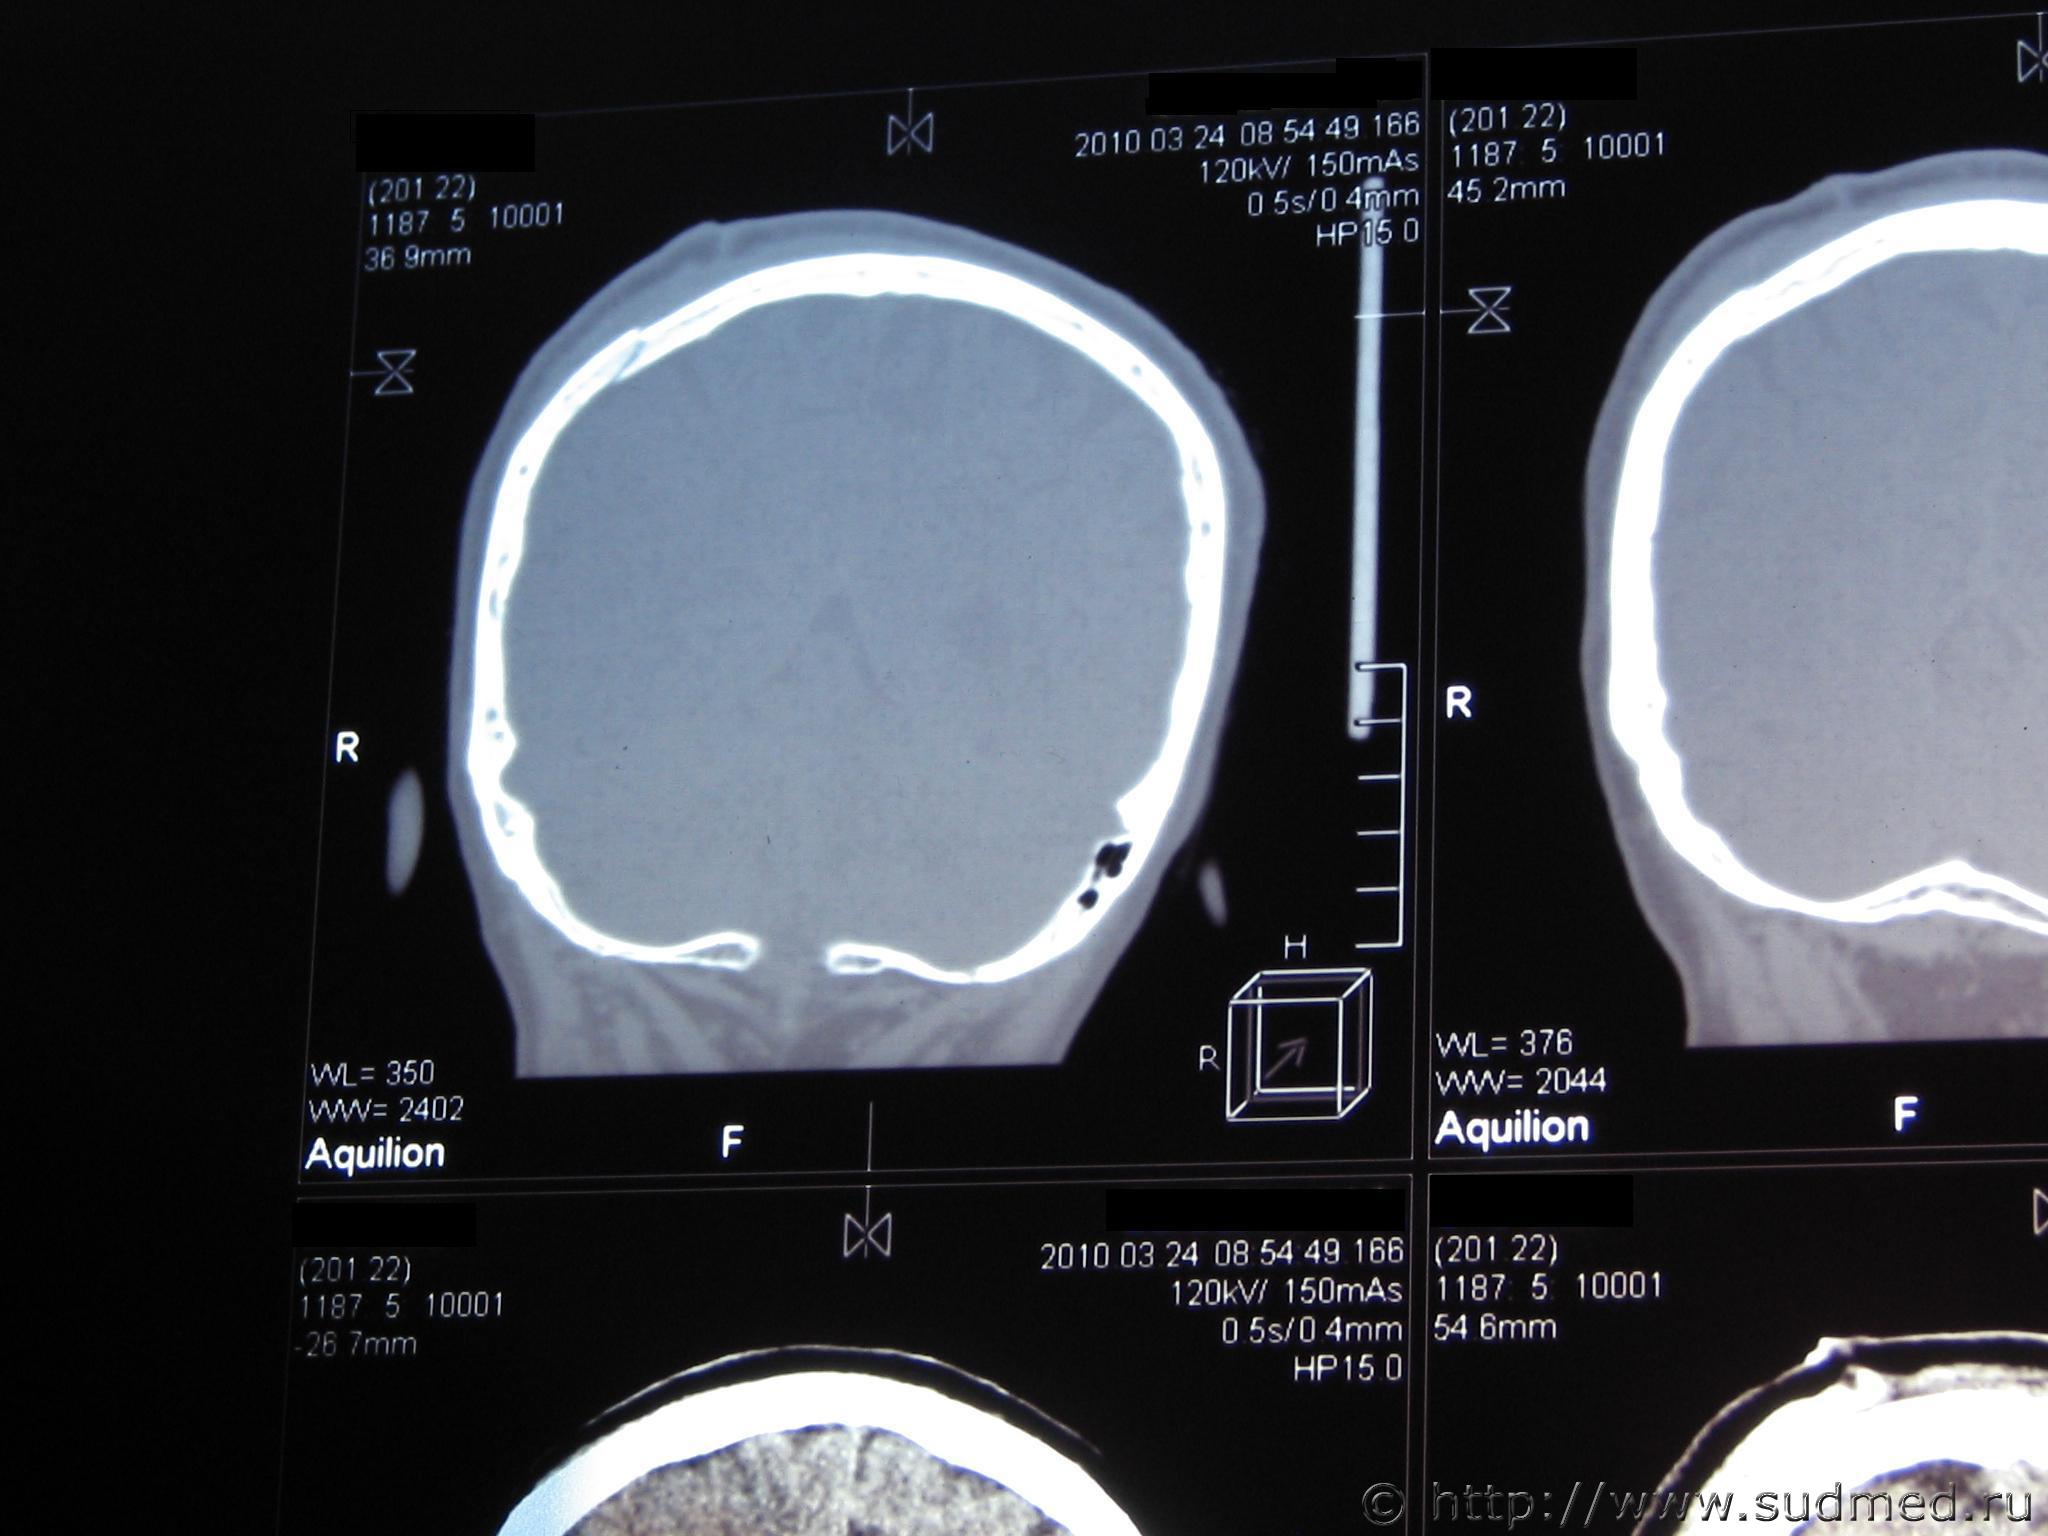

К выписке прилагается заключение по компьютерной томографии (см ct-resume.jpg)

Во вложении 2 снимка с томограммы - на них хорошо виден перелом

Слева вверху на ct1.JPG или первый и второй срез слева в верхнем ряду на ct2.JPG